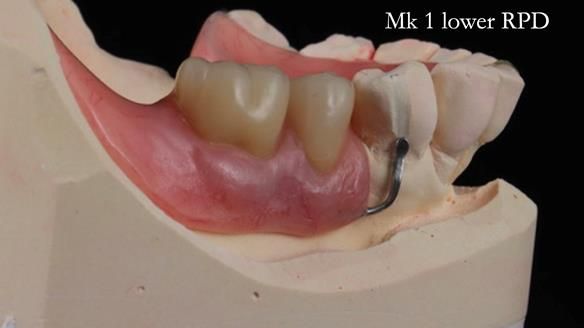

Welcome to my Newsletter 54 showing the making and fitting of dentures (a complete upper metal reinforced denture, a lower immediate partial denture and a definitive Scandinavian designed, metal based lower partial denture) for David, a 75 -year-old man. The full protocol workflow is presented including the use of dentate photographs to mimic his natural teeth.

The clinical situation and treatment process is shown in detail below. I provided the clinical work. Rowan Garstang, my dental technician, provided the technical work.

Interestingly we found that the upper complete denture when finished and fitted didn’t have good enough retention for David’s satisfaction. It was relined by adding compound to the buccal flanges – to almost overextend into the sulcus to ‘create’ a sulcus, followed by using a light bodied silicone impression material. This improved the function of the C/-considerably. A lower Scandinavian hygienically designed lower RPD was also provided which helped with occlusal stability and reseating the upper denture – further improving the fit.